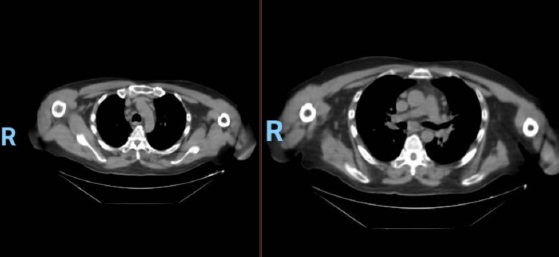

En la tomografía computada de tórax en ventana pulmonar se identifica un patrón micronodular con distribución perilinfática y difusa en ambos hemitórax. Este hallazgo se acompaña de un engrosamiento peribronquial notable, así como de opacidades en vidrio deslustrado, que predominan en las zonas subpleurales y en las regiones posteriores de ambos pulmones.

En la tomografía computada de tórax en ventana mediastínica se observan múltiples adenopatías localizadas en diversas áreas del cuello y mediastino. Estas adenopatías se distribuyen en las cadenas yúgulo-carotídeas, en ambas regiones supraclaviculares y a lo largo del mediastino, abarcando específicamente las siguientes áreas: la región paratraqueal superior derecha, los espacios retrocavo-pretraqueal y prevascular, la zona subcarinal, la ventana aortopulmonar y en la región de la arteria mamaria (AM). La presencia de estas adenopatías sugiere un compromiso linfático difuso en estas zonas.